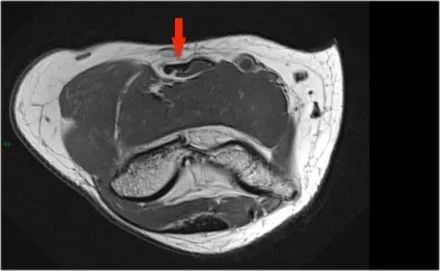

3.滑膜皱襞(plica)有时可以看到关节外侧的这种结构并且是一个皱褶。它可以是突出的,几乎看起来像半月板。这是一种正常的结构,但有时它会变厚或不规则,可能是症状的原因。